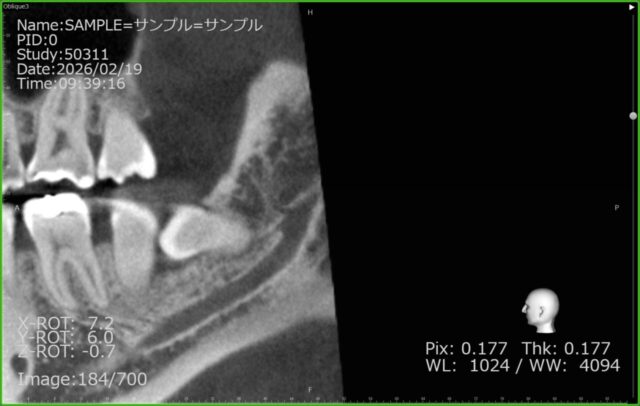

そこで当院では、より詳しく安全性を確認するために

コーンビームCT(CBCT)撮影を行いました。

CT画像では、

途中で枝分かれしている

神経が歯のすぐ近くを走行している

ことが確認できました。

このような解剖学的バリエーションは、

通常のレントゲンだけでは正確に把握することが困難です。